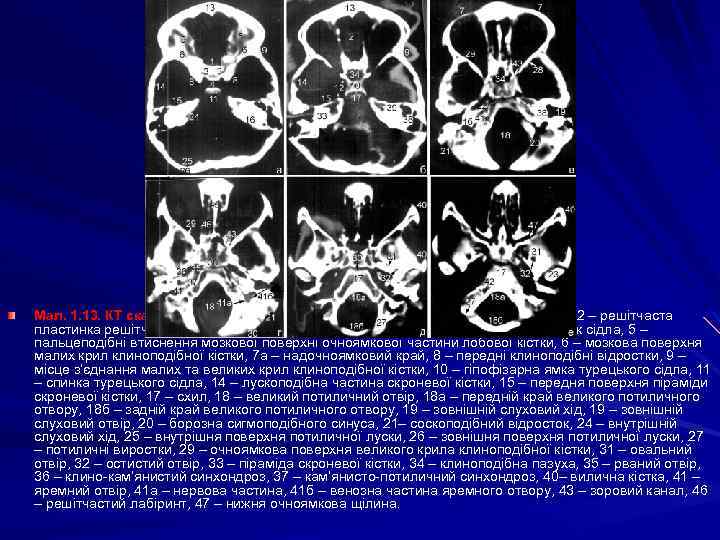

Компютерно-томографiчне дослiдження та анатомiя мозку КТ дослідження склепіння черепа в аксіальній проекції виконують починаючи від зовнішніх слухових ходів до тім’яних горбів. Склепіння черепа вище від тім’яних горбів не підлягає дослідженню в аксіальній проекції. На комп’ютерних томограмах, виконаних у коронарній (фронтальній) проекції в оптимальних умовах дослідження ї перебувають тім’яні кістки, великі крила клиноподібної та лускоподібна частина скроневої кістки. КТ дослідження склепіння черепа особливо доцільно використовувати для визначення глибини залягання патологічного процесу (кісткових відламків, осередків деструкції, склерозу, гіперостозу, ділянок звапнення тощо). КТ дослідження основи черепа переважно виконують в аксіальній проекції і за потреби доповнюють коронарними зрізами. Зрізи в аксіальній проекції виконують паралельно до верхньої орбіто-меатальної лінії, попередньо визначивши рівень сканування на топограмі черепа в бічній проекції.

Мал. 1. 13. КТ скани черепа в аксіальній площині. 1 – клиноподібне підвищення, 2 – решітчаста пластинка решітчастої кістки, 3 – край клиноподібного підвищення (лімб), 4 – горбок сідла, 5 – пальцеподібні втиснення мозкової поверхні очноямкової частини лобової кістки, 6 – мозкова поверхня малих крил клиноподібної кістки, 7 а – надочноямковий край, 8 – передні клиноподібні відростки, 9 – місце з’єднання малих та великих крил клиноподібної кістки, 10 – гіпофізарна ямка турецького сідла, 11 – спинка турецького сідла, 14 – лускоподібна частина скроневої кістки, 15 – передня поверхня піраміди скроневої кістки, 17 – схил, 18 – великий потиличний отвір, 18 а – передній край великого потиличного отвору, 18 б – задній край великого потиличного отвору, 19 – зовнішній слуховий хід, 19 – зовнішній слуховий отвір, 20 – борозна сигмоподібного синуса, 21– соскоподібний відросток, 24 – внутрішній слуховий хід, 25 – внутрішня поверхня потиличної луски, 26 – зовнішня поверхня потиличної луски, 27 – потиличні виростки, 29 – очноямкова поверхня великого крила клиноподібної кістки, 31 – овальний отвір, 32 – остистий отвір, 33 – піраміда скроневої кістки, 34 – клиноподібна пазуха, 35 – рваний отвір, 36 – клино-кам’янистий синхондроз, 37 – кам’янисто-потиличний синхондроз, 40– вилична кістка, 41 – яремний отвір, 41 а – нервова частина, 41 б – венозна частина яремного отвору, 43 – зоровий канал, 46 – решітчастий лабіринт, 47 – нижня очноямкова щілина.